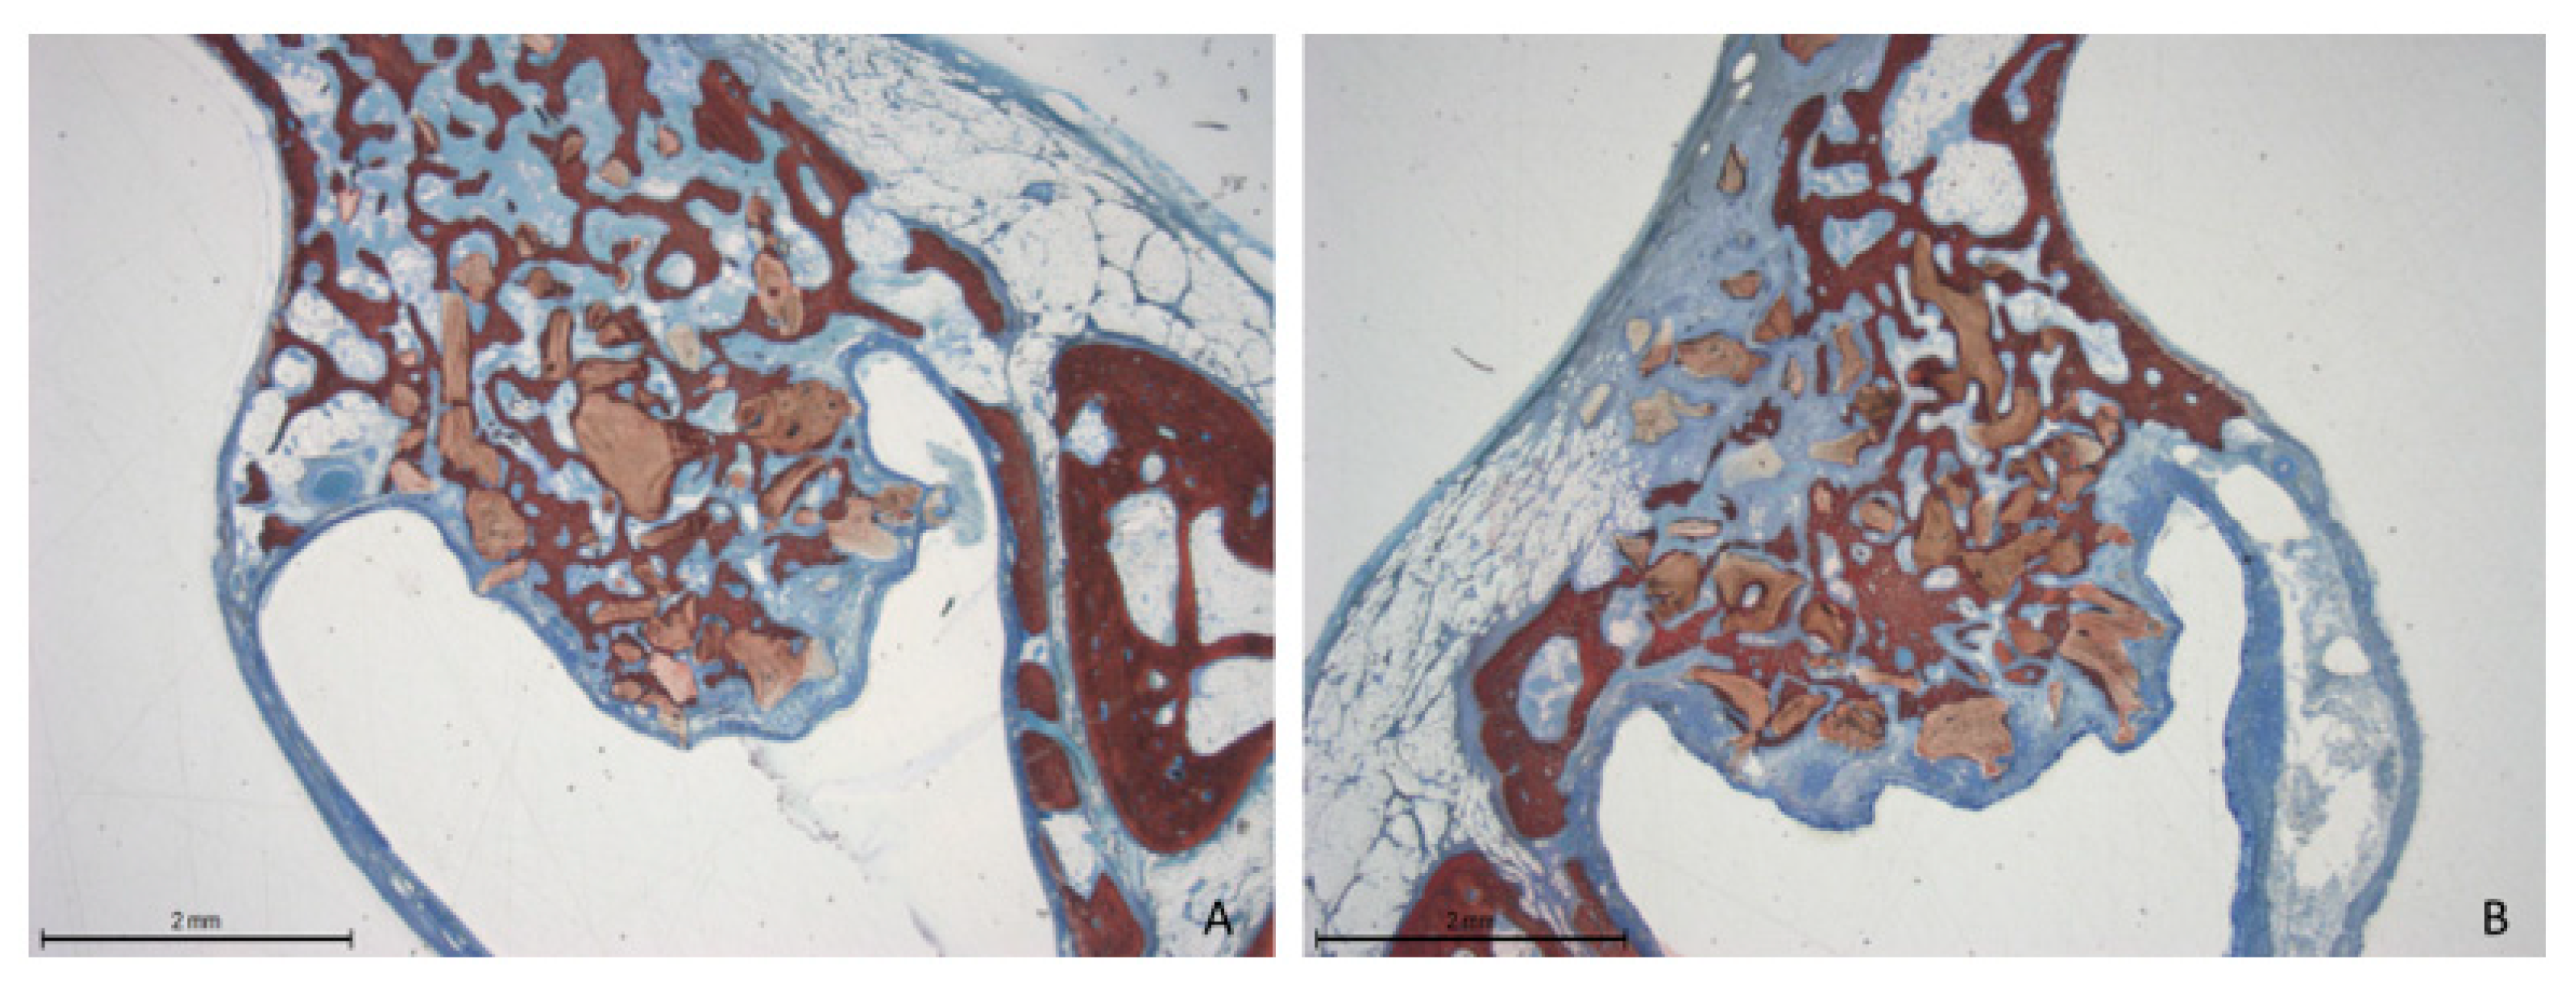

Two weeks post-healing, the histological features within the elevated space appeared similar between the collagenated and non-collagenated groups (Figure 3A,B).

Figure 3.

Photomicrographs of ground sections after 2 weeks of healing. (A) Collagenated site; (B) non-collagenated site. The histological analysis revealed similar features in both the collagenated and non-collagenated groups, with new bone predominantly observed near the bone window and minimal presence in other areas. Staining was performed using Stevenel’s blue and alizarin red stain.

At the 12-week time point, there was an increase in new bone formation across all evaluated areas compared to the previous period. However, no signs of corticalization were observed beneath the sinus mucosa. In some instances, an attempt at closure of the access window was noted (Figure 8A,B).

Figure 8.

Photomicrographs of ground sections after 12 weeks of healing. The histological features were similar between the collagenated and non-collagenated groups. A significant increase in new bone formation was evident across all the evaluated areas. (A) Collagenated site; (B) non-collagenated site. Staining was performed using Stevenel’s blue and alizarin red stain.